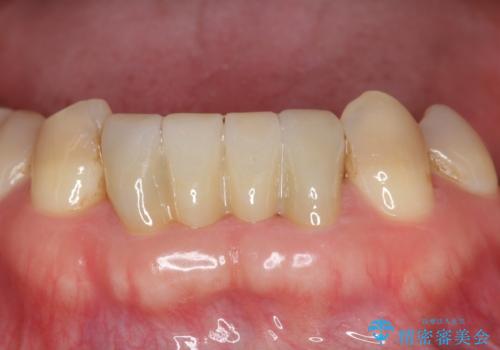

下の前歯のブリッジ 保険治療のやり替え

- 前歯のブリッジのやり替えをご希望されました。

かみ合わせが強く、以前入っていた保険治療のブリッジも前装が欠けてしまっていました。

セラミックも強い衝撃で欠けないわけではないため、強度のあるフルジルコニアクラウンでブリッジを作成しました。

フルジルコニアクラウンはやや白すぎるといった難点がありますが、今回は強度を優先することにしました。